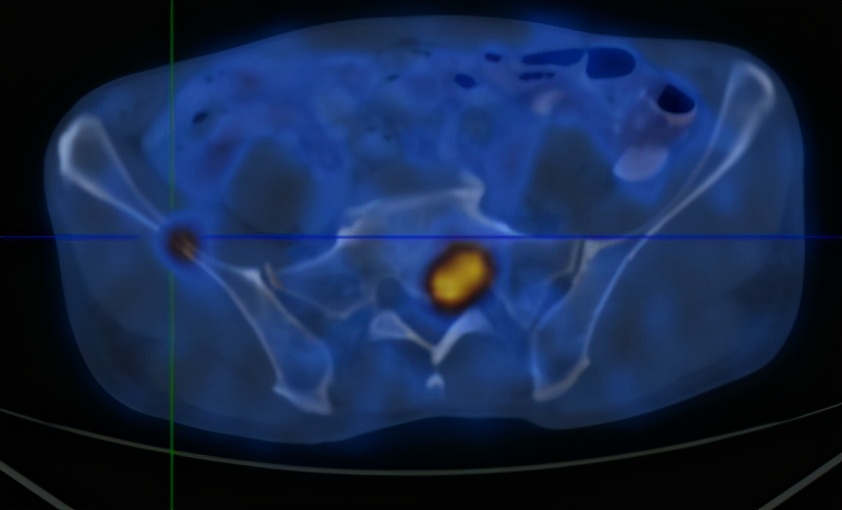

2020-6-19患者行全身PET/CT示:

1、左下肺前内基底段支气管开口处结节,糖代谢增高,考虑中央型肺癌并远端阻塞性炎症、不张;全身(双侧颈部、双侧锁骨上下窝、两侧肺门、纵隔、贲门旁、胰头后方、腹主动脉旁及双侧髂血管旁)多发淋巴结转移;双肺多发转移;肝S4及S5转移;胰头部结节转移;全身多发骨转移;综上,建议活检除外结核。

2、甲状腺双侧叶多发结节,糖代谢增高,不除外恶性肿瘤,建议追踪。左侧肾上腺稍增粗,糖代谢轻度增高,建议追踪。

3、前列腺钙化灶。右侧阴囊钙化灶。

4、心包少许积液。